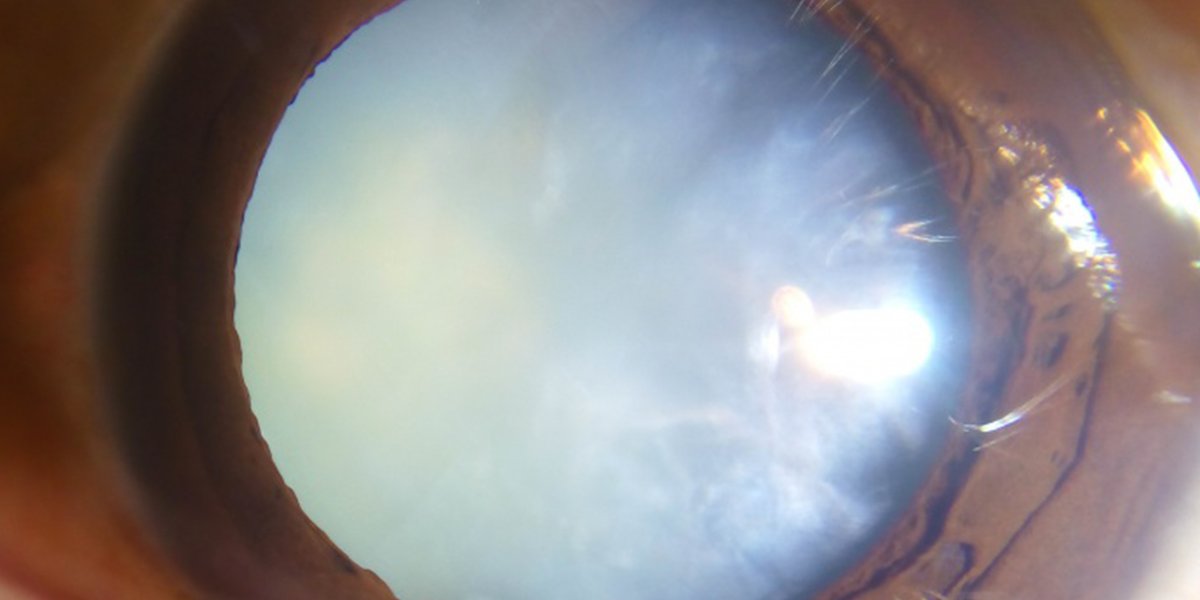

#Cataract Awareness Month: There are several types of cataract including age-related, traumatic, and metabolic. Age-related cataract is the most common and the pathogenesis is multifactorial and not fully understood. #ophthalmology https://t.co/oe69mkz4Yd